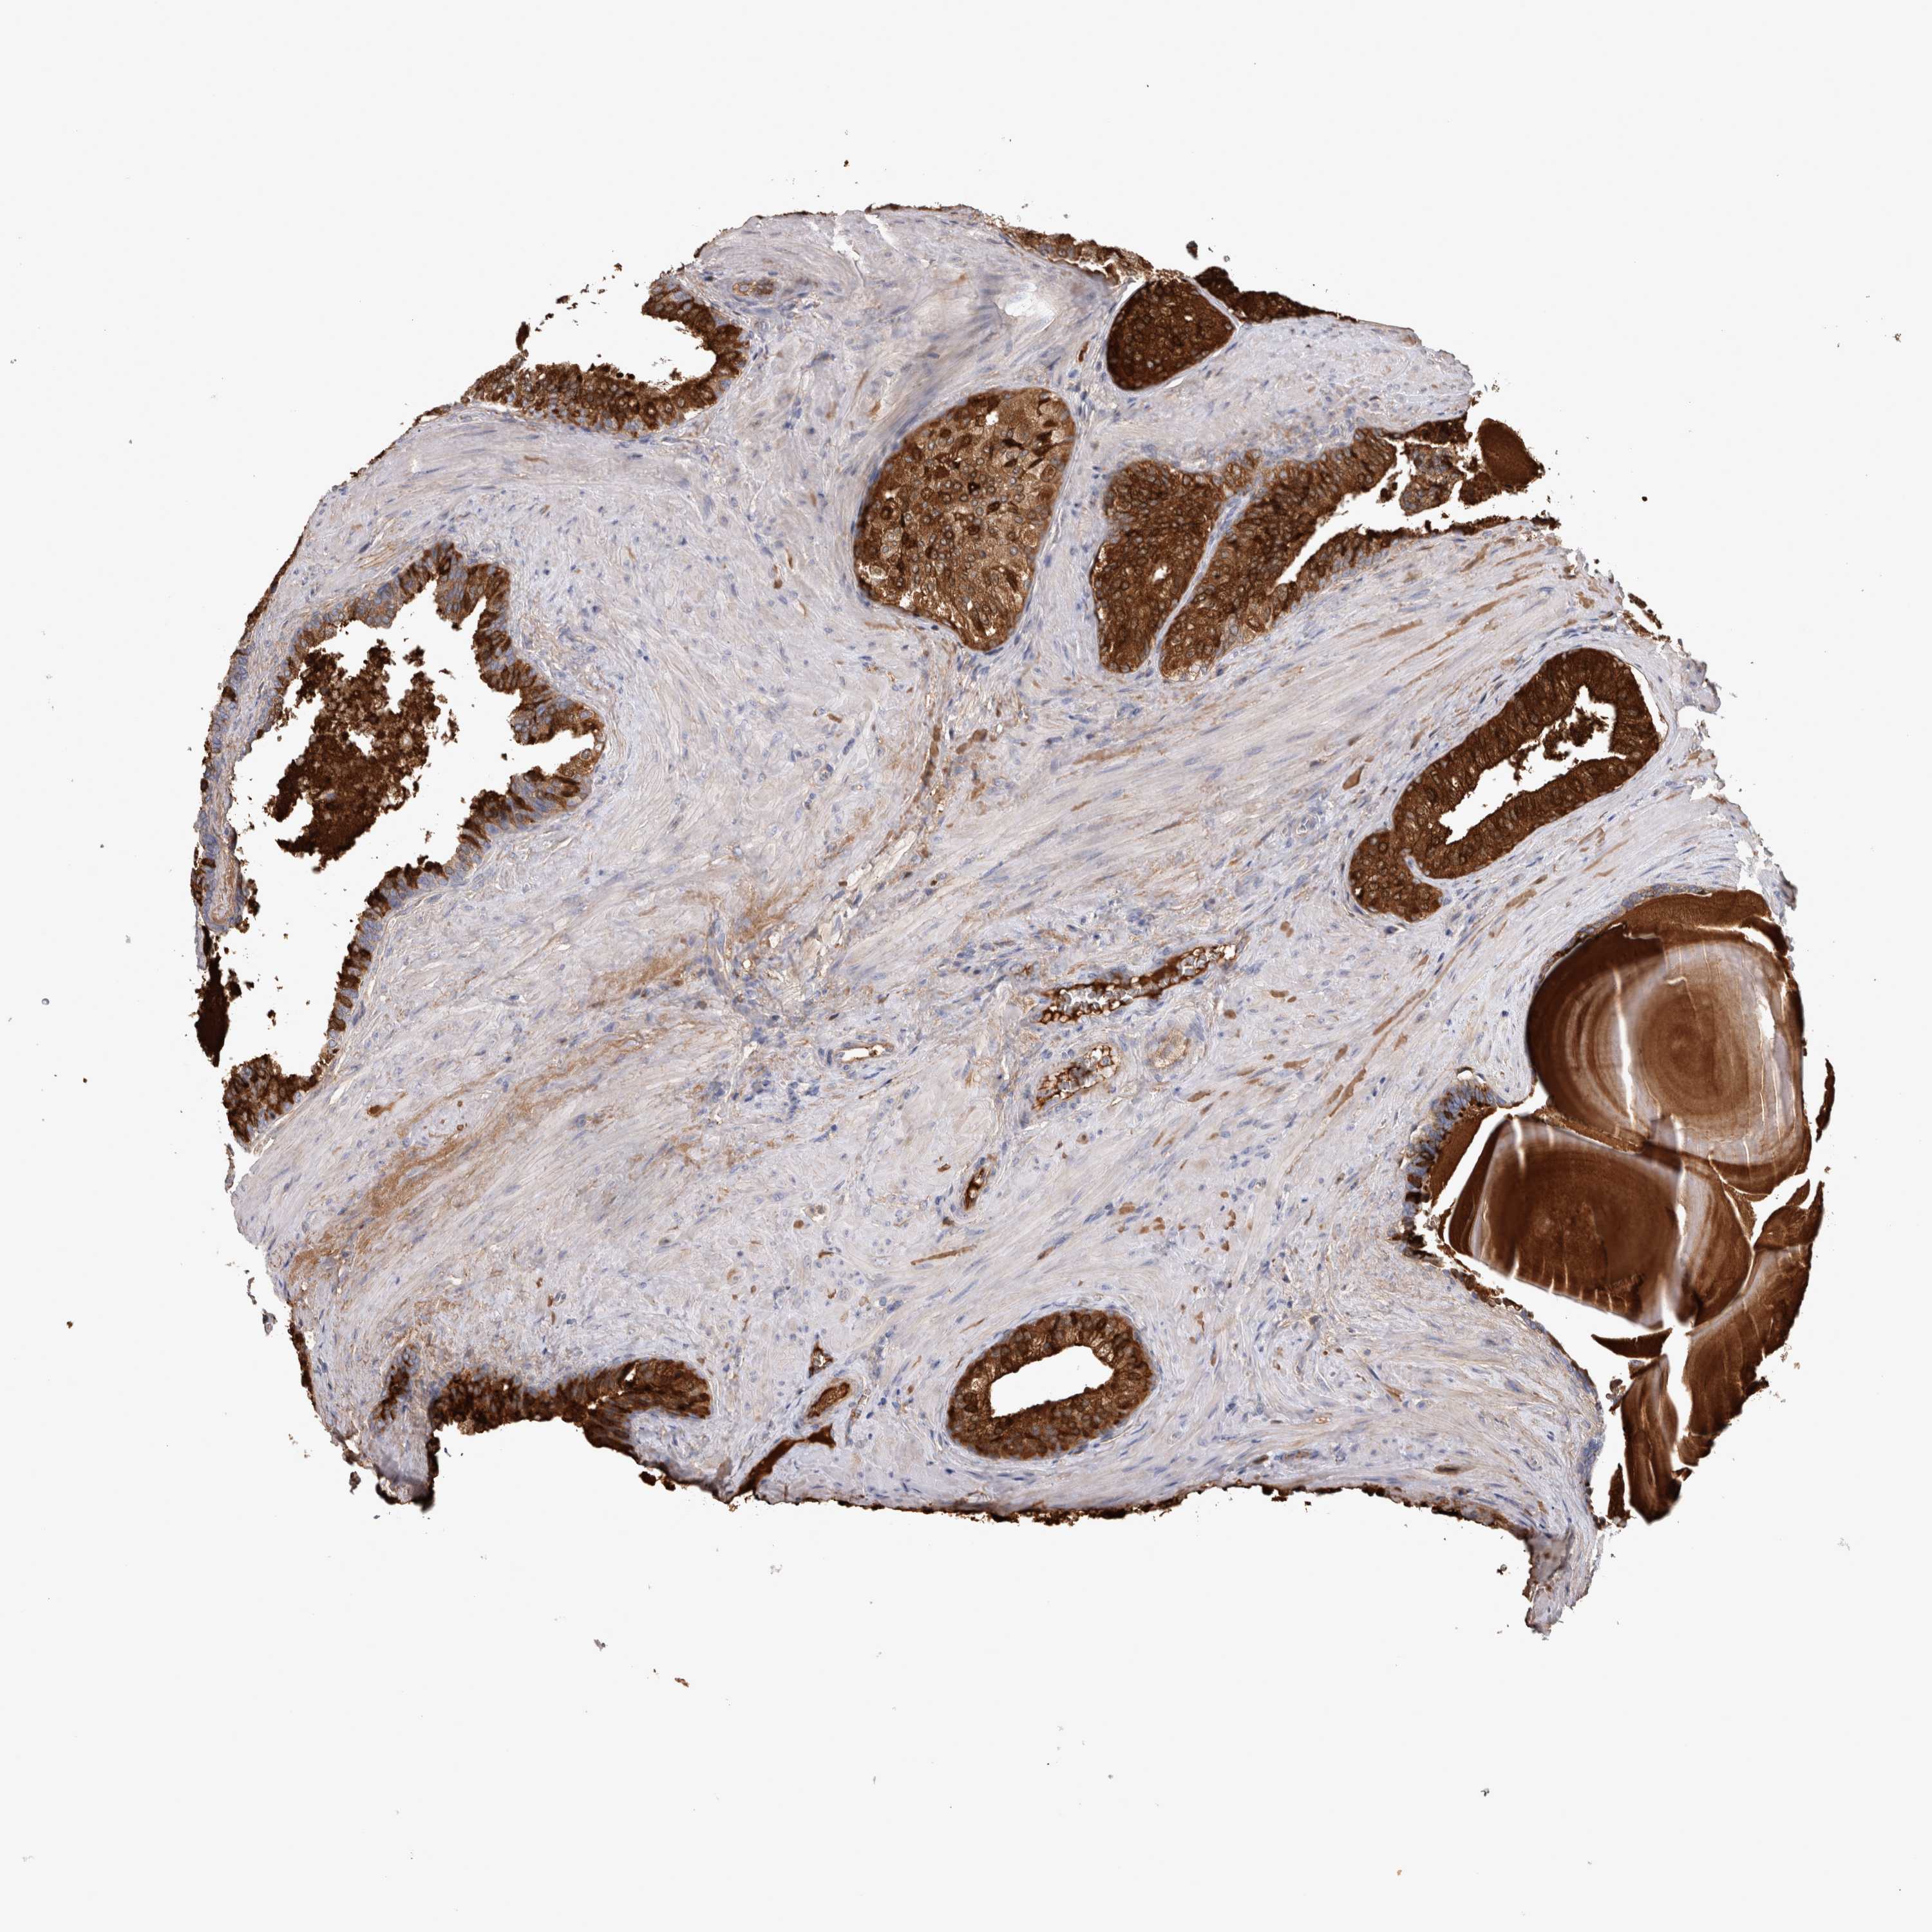

PROSTATE CANCER - Protein expressioni

A mouse-over function shows sample information and annotation data. Click on an image to view it in a full screen mode. Samples can be filtered based on level of antibody staining by selecting one or several of the following categories: high, medium, low and not detected. The assay and annotation is described here.

Antibody stainingi

Antibody staining in the annotated cell types in the current human tissue is reported as not detected, low, medium, or high, based on conventional immunohistochemistry profiling in selected tissues. This score is based on the combination of the staining intensity and fraction of stained cells.

Each image is clickable and will lead to virtual microscopy that enables deeper exploration of all samples and also displays staining intensity scores, fraction scores and subcellular localization as well as patient and tissue information for each sample.

Antibody HPA051257

Antibody CAB026357

Staining

High

Medium

Low

Not detected

Intensity

Strong

Moderate

Weak

Negative

Quantity

>75%

75%-25%

<25%

None

Location

Nuclear

Cytoplasmic/membranous

Cytoplasmic/membranous,nuclear

Adenocarcinoma, High grade

Adenocarcinoma, Medium grade

Adenocarcinoma, Low grade